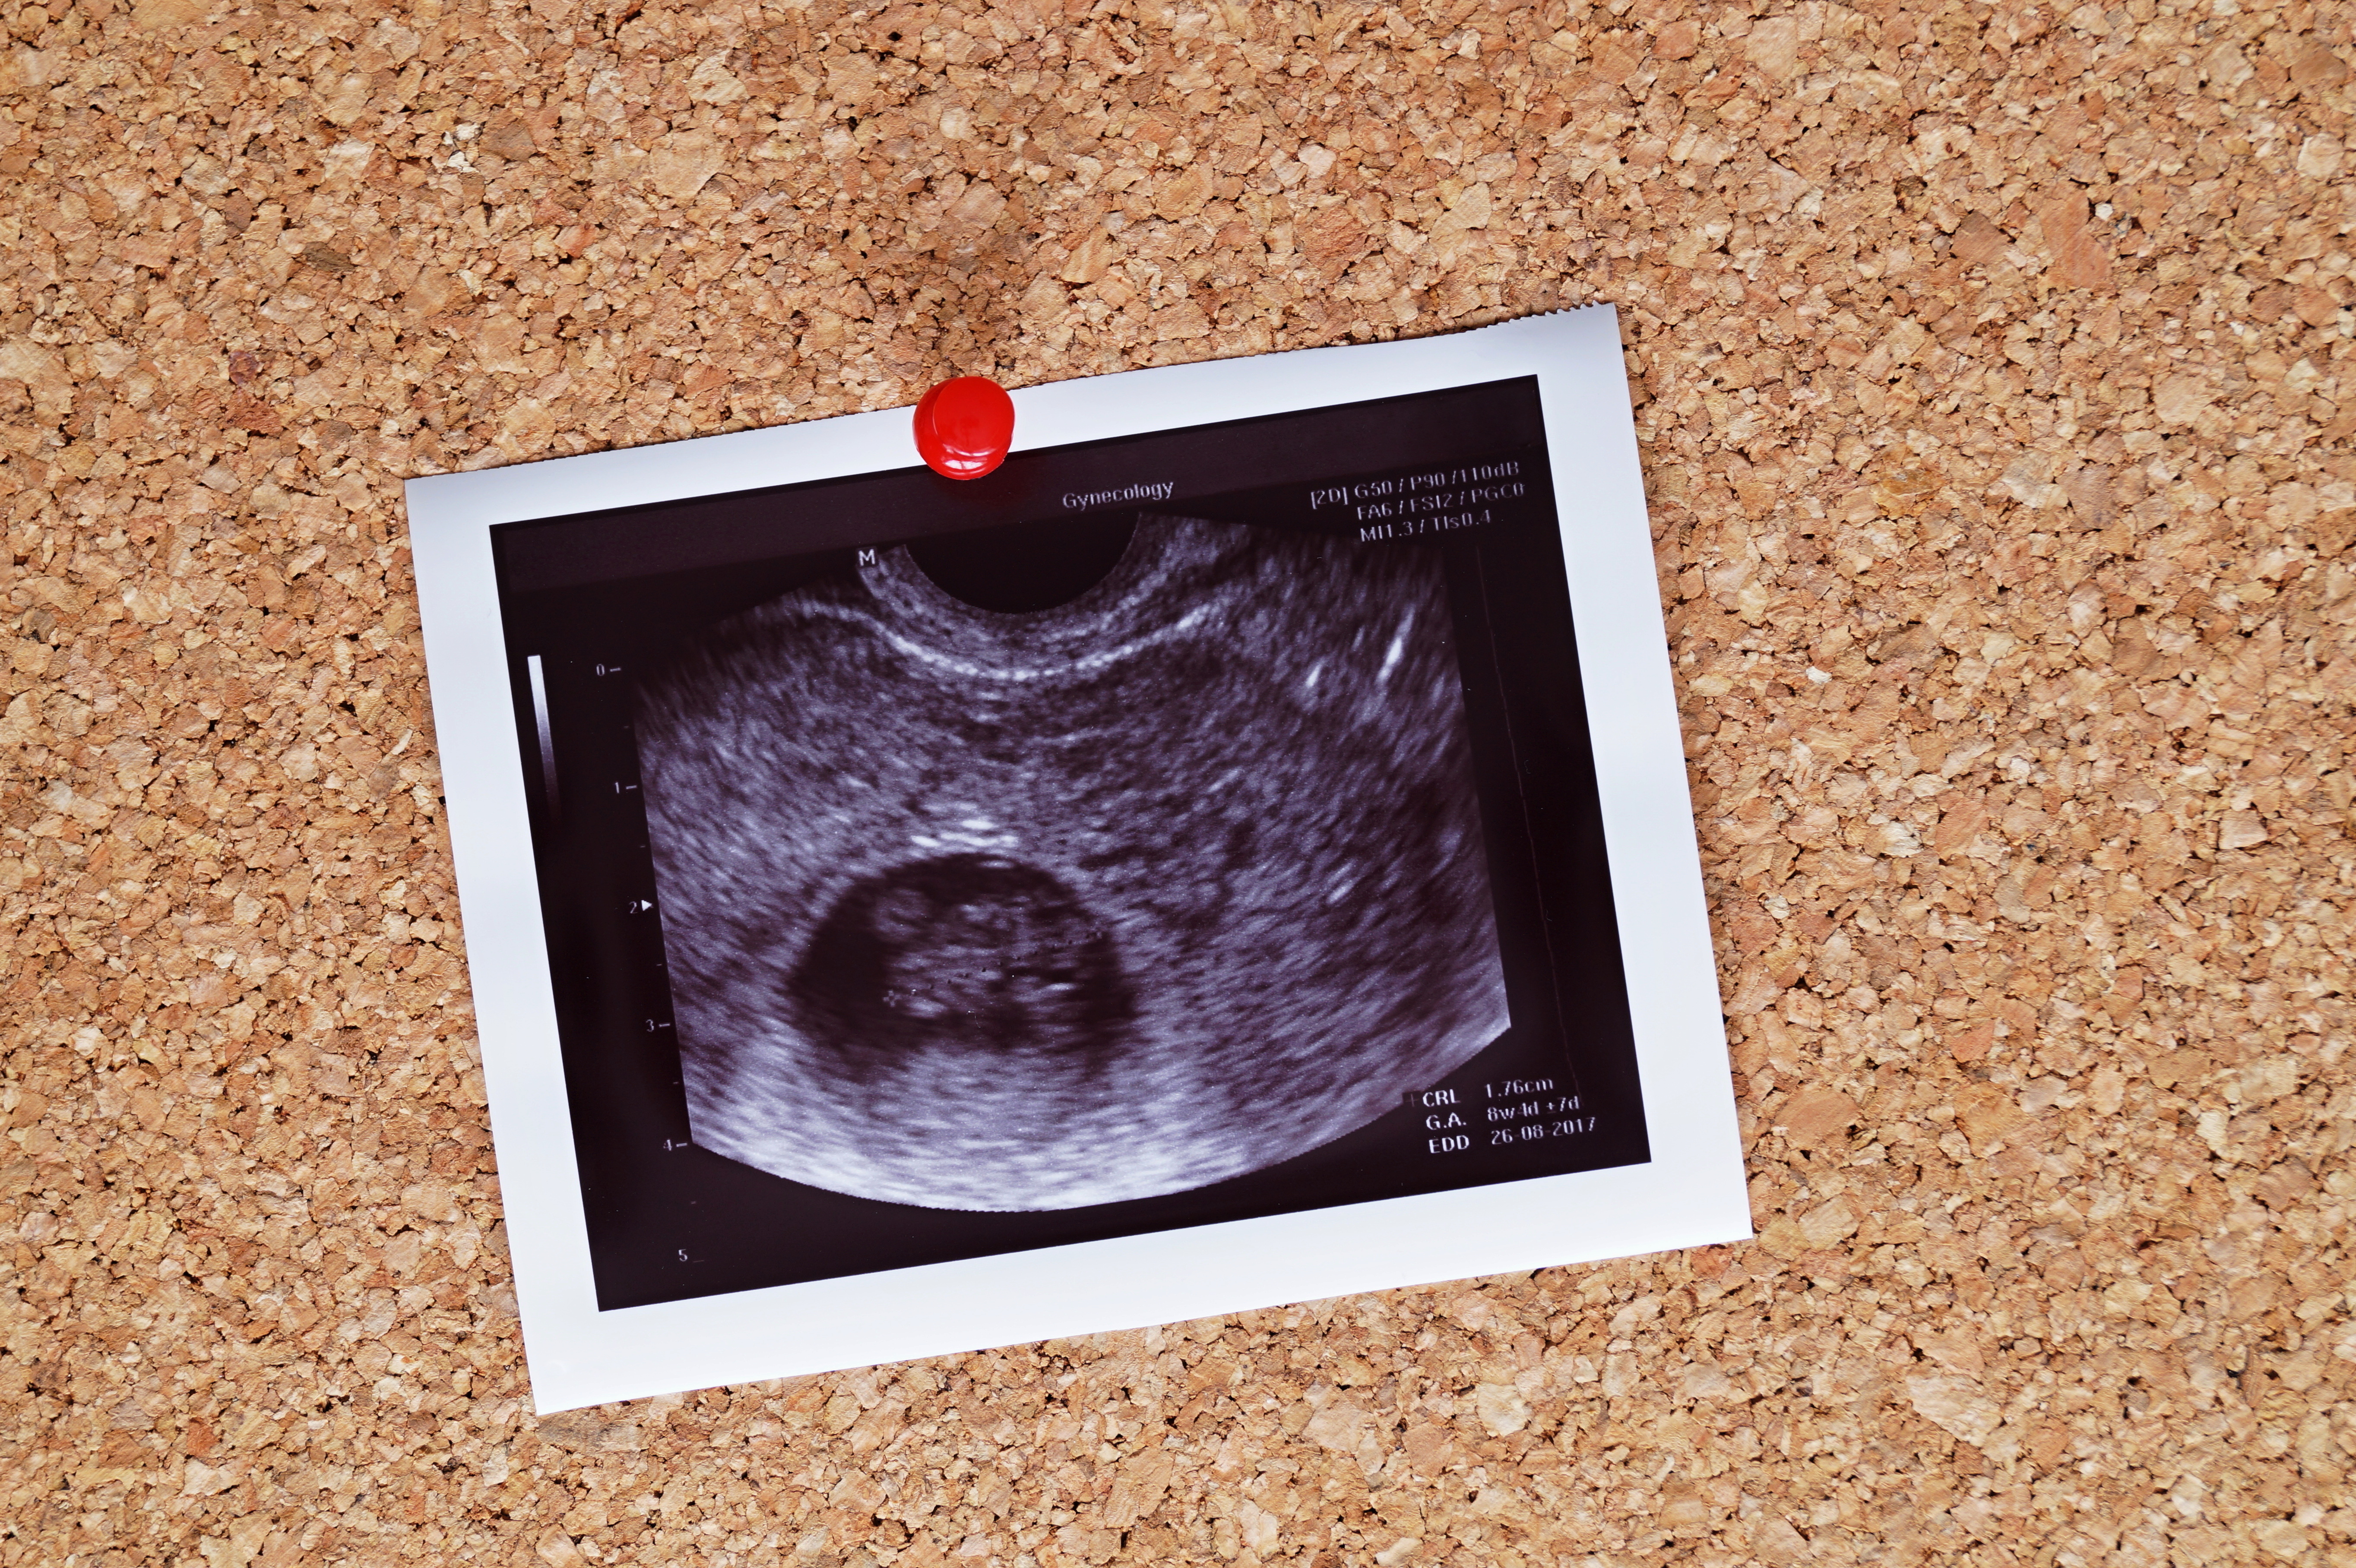

胎児の大きさがはっきり測れる時期

妊娠初期の赤ちゃんの発育には個人差がほとんどないのですが、妊娠9週になると赤ちゃんの大きさをはっきりと測ることができるようになます。頭臀長(とうでんちょう)という赤ちゃんの頭からお尻までの長さを健診のたびに測り、成長が順調かを診るようになるのです。

頭殿長を測ると、妊娠9週ごろに最初に告げられた出産予定日にズレが出てくる場合があります。エコー写真に記されている出産予定日に誤差が出ていたら、赤ちゃんの成長の具合に個人差が出てきたのだと理解しておきましょう。

妊娠9週の赤ちゃんの大きさ

妊娠9週の赤ちゃんは、「身長:19mm~27mm」「体重:約3g~12g」程度に成長しました。エコーでは人間らしい二頭身の姿が見えるかもしれません。これまで心拍が確認できなかった人も、そろそろ心拍の確認ができるようになってくるころです。前のめりに曲がっていた頭がまっすぐに伸び、さらに人間らしくなってきました。

エコーでも、これまで見分けがつきにくかった頭と胴体の違いがわかることがあるでしょう。見た目にも赤ちゃんらしくなり、ますますエコーを見るのが楽しみになってきますね。